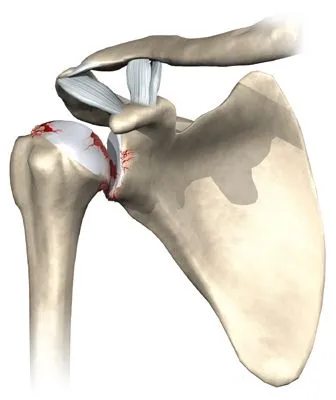

Les prothèses anatomiques sont des implants qui vont remplacer l'anatomie native des surfaces articulaires de la tête humérale et de la cavité glénoïdale.

L'implant huméral est composé d'une tige prothétique qui va etre insérée dans l'humérus et d'une "calotte" qui vient remplacer la tête humérale. Ces implants sont en titane ou en alliage chrome-cobalt.

L'implant glénoïdien est en polyéthylène. Il s'agit d'une matière plastique très resistante.

Pour que l'on puisse proposer une prothèse anatomique, il faut impérativement que les tendons de la coiffe des rotateurs soient sains et fonctionnels.